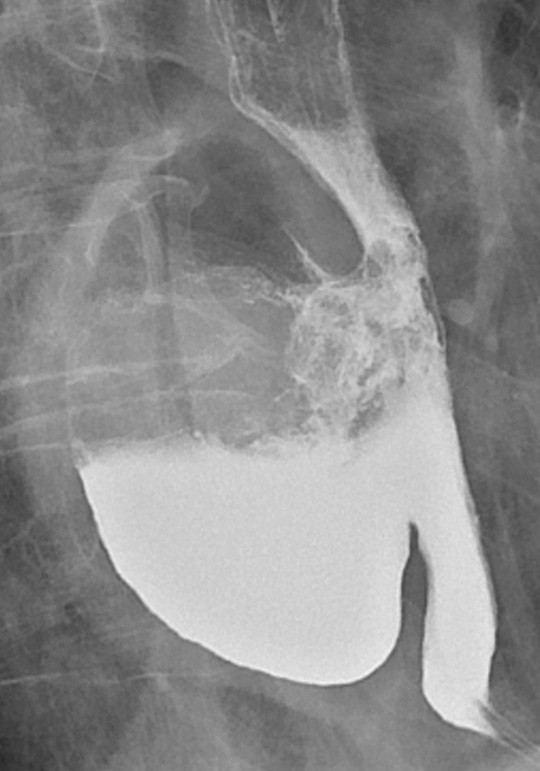

Postoperativ liggetid var median 16,5 dager (spredning 5 – 45 dager). For de åtte pasientene uten alvorlige komplikasjoner var det ti dager (5 – 16 dager). Største lengde av ekstirpert divertikkel (fig 1) var median 5 cm (spredning 3,5 – 9 cm). Halsen av divertikkelen mot oesophagus målte median 3 cm (spredning 1,5 – 5 cm).